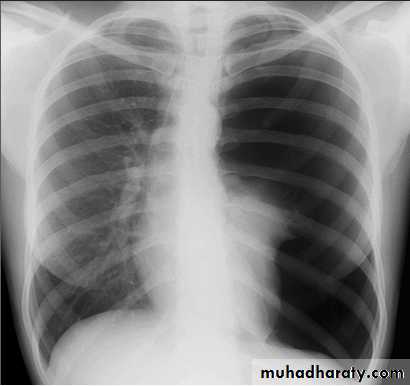

Pleural effusionX-ray of pleural effusion

Massive right effusion